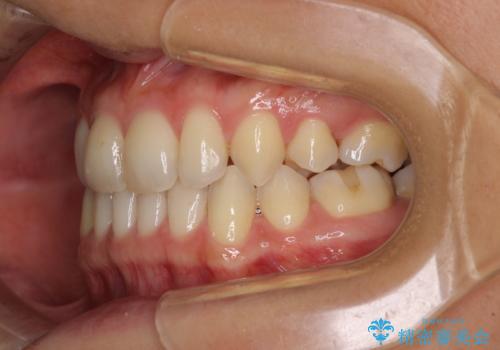

隙間の空いてしまった前歯は、矯正治療で治療を行っても後戻りが起こりやすい傾向にあります。

マウスピースの保定装置をしっかりと装着しても空いてしまうため、細いワイヤーによる保定を併用することで後戻りを防止しています。